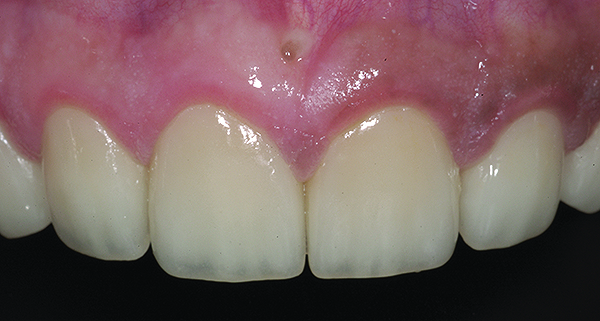

Figure 16. Anterior final restorations bonded.

Figure 16

The anterior restorations were fabricated with low-translucency lithium-disilicate ingots and layered in the incisal half to provide the desired internal characteristics in accordance with the patient’s age. The final anterior restorations were then tried-in and verified for marginal fit, esthetics, and phonetics. After the patient’s approval, they were bonded using dual-cured resin cement (Variolink® II, Ivoclar Vivadent) (Figure 16). Because the enamel in such cases is already compromised, bonding can become clinically unpredictable. A self-etching primer was used on the teeth, followed by a bonding agent (Clearfil™ ST Bond, Kuraray Dental, www.kuraraydental.com) that was light-cured for 20 seconds. The intaglio of the crowns was prepared by etching with 9% buffered hydrofluoric acid for 60 seconds and silanating them to achieve optimum bonds to the resin cement.18

The final restorations depicted restoration of form, function, and beauty, with good harmony of restoration and the periodontium (Figure 19 through Figure 25). MIP was in harmony with CR, and right and left lateral excursion discluded all posteriors with anterior group function. The postoperative orthopantomogram (OPG) (Figure 26) shows the treatment done while maintaining the vitality of anterior teeth.